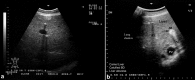

In camels, hepatic diseases are relatively common and most of them are misdiagnosed as a cause of illness because signs may be subtle. In addition, diagnostic laboratory methods are insufficient as hepatic enzymes can also be elevated in camels with cardiac or skeletal muscle damage. Examples of liver diseases in camels are hepatic lipidosis, hepatitis, cirrhosis, hepatic necrosis, choleostasis, hyperplasia of biliary epithelium, hydatid cysts, glycogen deposition, cholangitis, cholangiohepatitis, calcified hydatid cyst and hepatic abscesses. When the liver is examined by ultrasonography, the clinician gets sufficient information about the size, position, echopatterns of the hepatic parenchyma, bile ducts and outlines of the hepatic blood vessels. Ultrasonography has been used previously in camels only for reproductive purposes. However, during the past decade, it has been used for scanning of the healthy organs as well as evaluation and determining the diagnosis and prognosis of non-reproductive disorders. Examples of diseases evaluated by ultrasonography in camels are paratuberculosis, trypanosomiasis, abdominal and urinary disorders, thoracic diseases, renal tumors, pyelonephritis, renal abscessation, gastrointestinal tumors, chronic peritonitis and splenic abscessation. Ultrasound-guidance in biopsy of hepatic lesions and in portocentesis has also been reported in camels. This mini review article is written to shed light on ultrasonography of the liver and its blood vessels in healthy camels as well as finding in camels with hepatic disorders such as fatty infiltration of the liver, hepatic abscesses and calcification of the bile ducts.